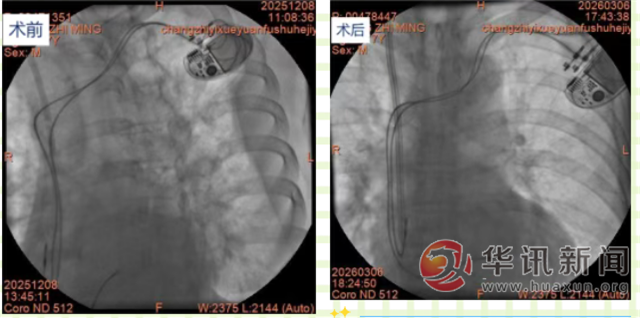

手术当日,在DSA室精准影像引导下,肾内科手术团队凭借扎实的专业功底和丰富的复杂手术操作经验,术中全程实时监测起搏器工作状态,心内科王俊莉主任团队全程值守,密切关注各项生命体征变化。经过医护团队的紧密配合与精准操作,仅用1小时便顺利完成手术,导管位置精准达标,未对永久起搏器导线造成任何影响,患者术中无明显不适,生命体征全程平稳。